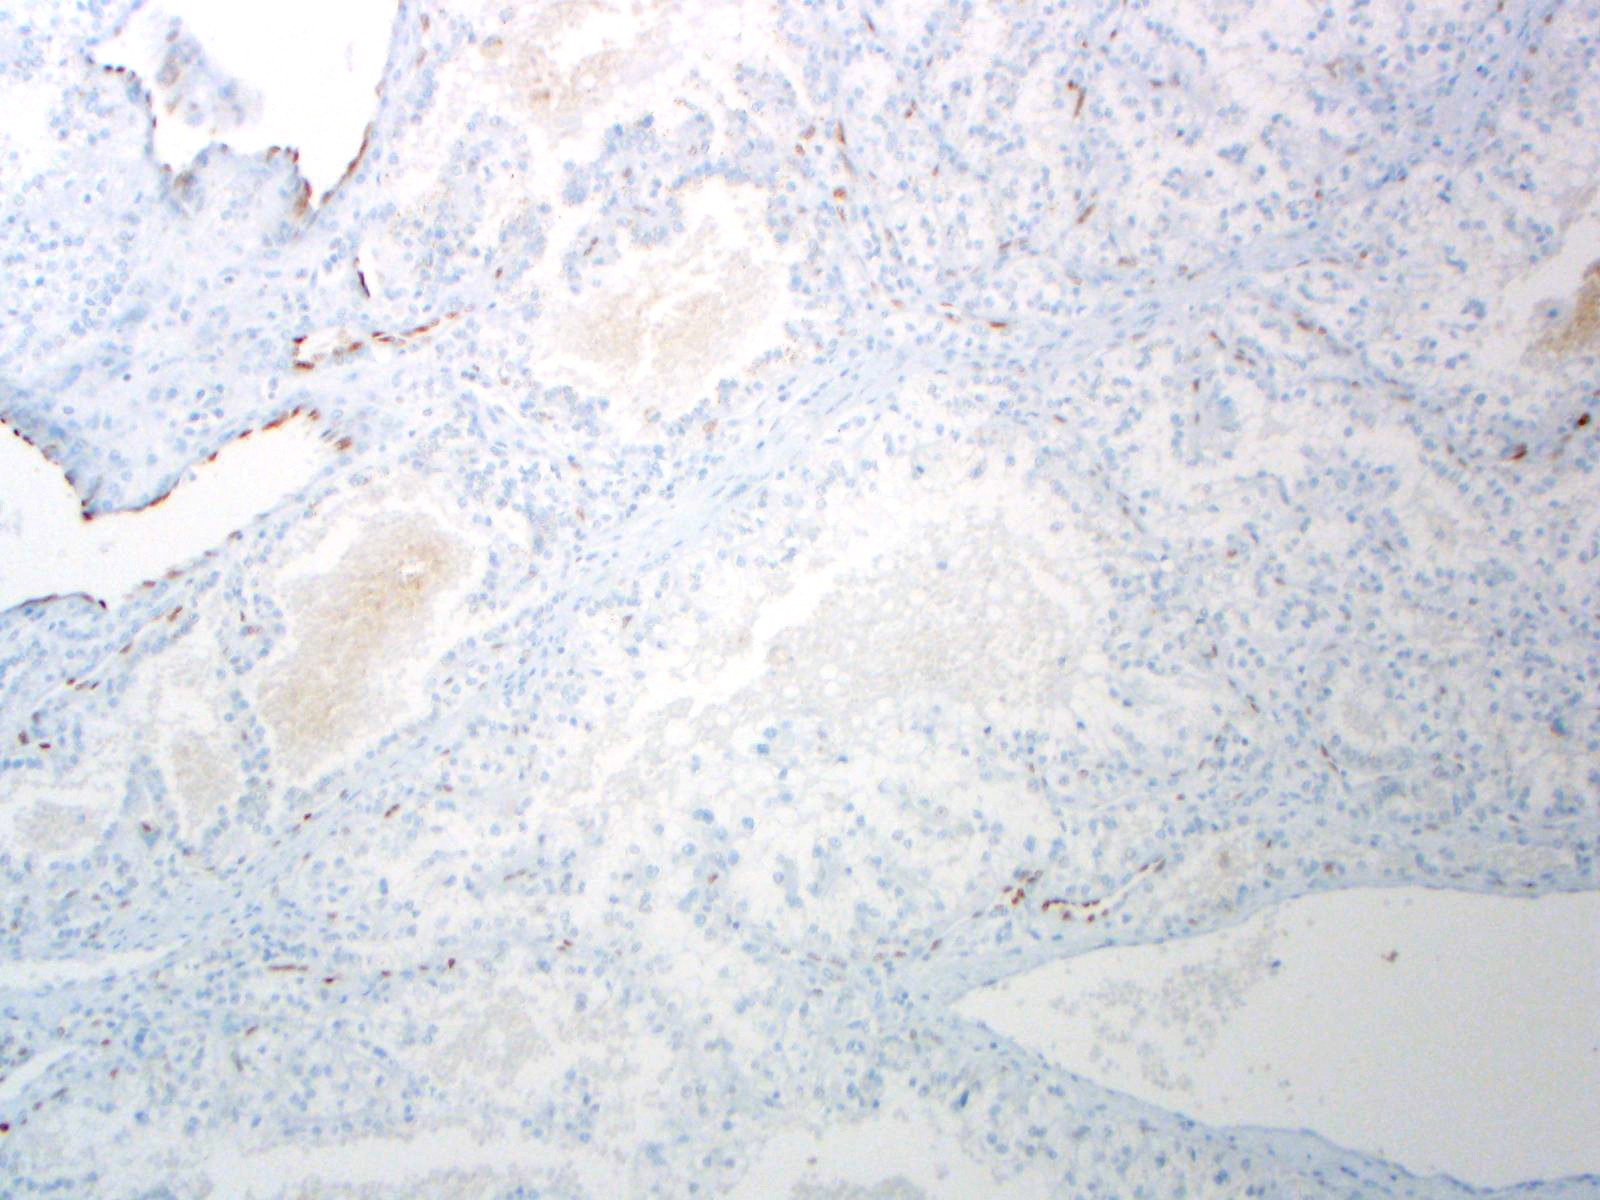

| 2SC |

S-(2-succino)-cysteine |

Hereditary leiomyomatosis and renal cell carcinoma (HLRCC) syndrome-associated RCC and leiomyoma

Most renal tumors and leiomyomas not associated with HLRCC

Staining Pattern

Cytoplasmic and nuclear

| HLRCC-associated RCC |

| Non-HLRCC-associated RCC |